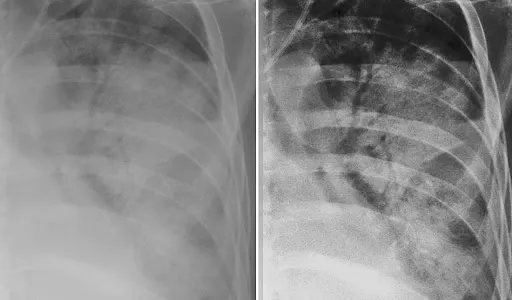

1. Static vs Dynamic Air Bronchogram with Dr. Aisha Khan

Ever confused between obstructive atelectasis and pneumonia? This video explains it with real-time lung ultrasound footage.

• Difference between static and dynamic air bronchograms

• HRCT and ultrasound correlation

• Clinical significance with live interpretation